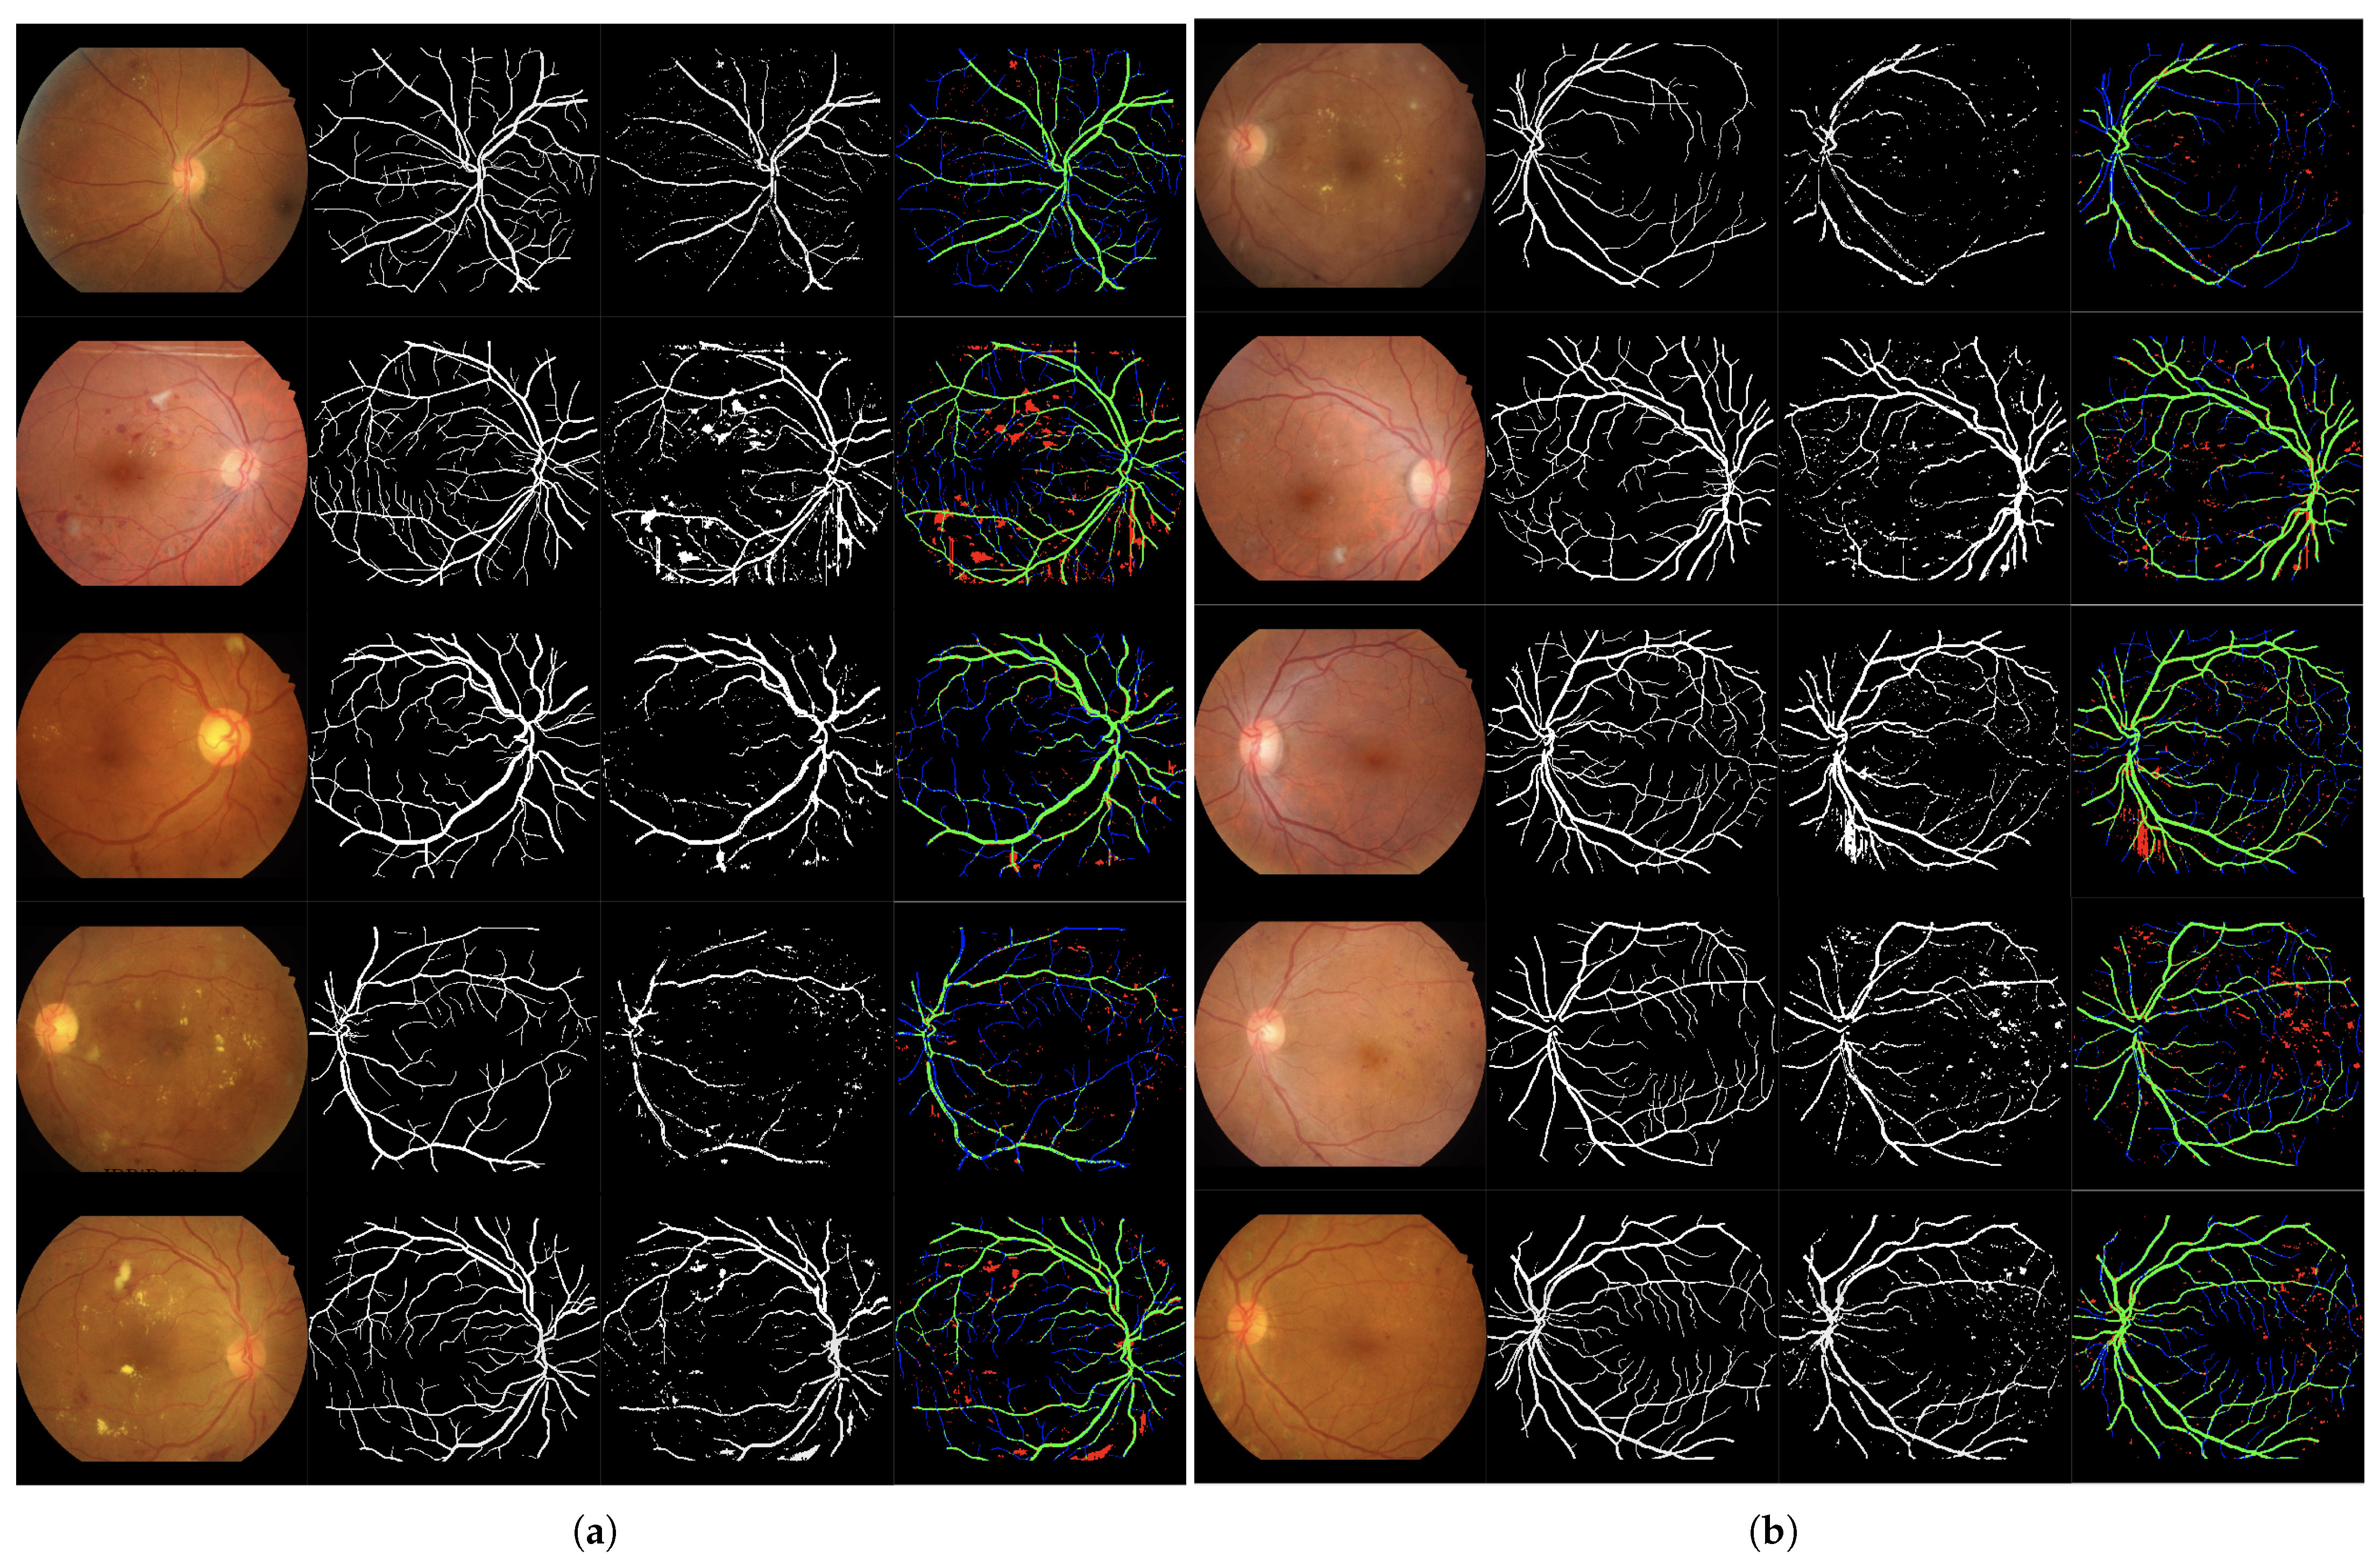

Figure 6.

Set of 4-image sequences illustrating the test results of Experiment 2 graphically. The first image is the original input, the second shows the ground truth vessel locations labeled by experts, the third corresponds to the output of the ANN from experiment 2, and the fourth visualizes the outcome in terms of true positives (green), false positives (red), false negatives (blue), and true negatives (black). Panel (a) displays the first five test images, while panel (b) shows the last five.